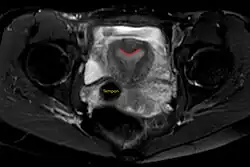

| Arcuate uterus (marked in red) seen on MRI | |

The arcuate uterus is a form of a uterine anomaly or variation where the uterine cavity displays a concave contour towards the fundus. Normally the uterine cavity is straight or convex towards the fundus on anterior-posterior imaging, but in the arcuate uterus the myometrium of the fundus dips into the cavity and may form a small septation. The distinction between an arcuate uterus and a septate uterus is not standardized.